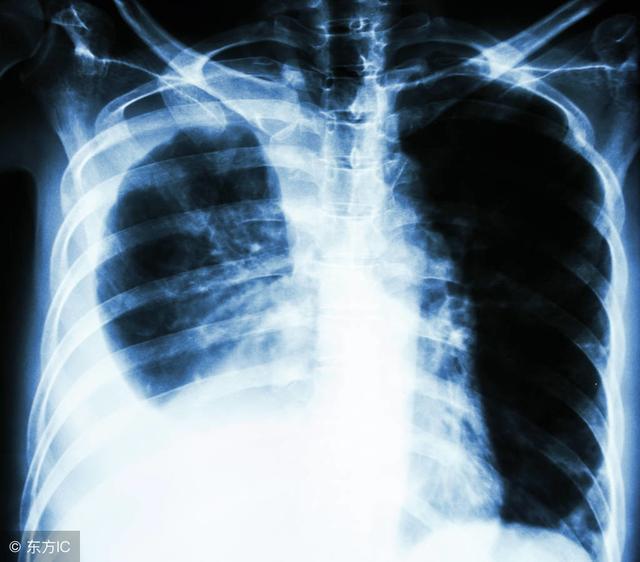

结核性胸膜炎是怎么引起的?(胸膜炎症状)

最近这几年老年人胸腔积液出现几率较高,而且原因复杂,常常伴随这一些不明的原因,那么老年人胸腔积液与胸膜炎是由什么原因引起的,发病机制又是什么呢?下面就为大家介绍一下。

老年胸腔积液的病因十分复杂,大致上可以分为三大类:①漏出性:常见于心血管疾病,如心力衰竭、缩窄性心包炎、上腔静脉梗阻等;肝肾疾病合并低蛋白血症时。②渗出性:常见于感染性炎症,如结核、病毒、化脓性细菌、真菌、寄生虫等;恶性肿瘤,包括原发肺癌、肺转移癌、淋巴癌及胸膜间皮瘤等;变态反应性炎症,如系统性红斑狼疮、类风湿性关节炎等;化学性炎症,如尿毒症等。③血性:常见于恶性肿瘤、肺梗死、外伤等。

胸腔内的液体动态平衡=滤过系数×[(平均毛细血管静水压-平均毛细血管周静水压)-(血浆胶体渗透压-毛细血管周胶体渗透压)]。正常情况下胸腔内液体从胸膜(主要是壁层胸膜)毛细血管的动脉端流出,其80%~90%从毛细血管的静脉端吸收,剩余部分经淋巴系统回收。当平均毛细血管静水压上升时,如心力衰竭;或血浆胶体渗透压降低时,如慢性肝肾疾病;或毛细血管胶体渗透压上升时,如胸膜炎症使毛细血管透过性增加,大量蛋白质外渗。上述因素均可使胸腔内液体的流出量超过回收量而形成胸腔积液。恶性肿瘤侵蚀血管,血液有形成分及蛋白质外漏使毛细血管周胶体渗透压升高,它还可能压迫阻塞淋巴管使平均毛细血管静水压上升。

随着我国老年人的逐渐增多,老年人胸腔积液与胸膜炎的发生率也会增高,所以更需要大家了解老年人胸腔积液与胸膜炎的引发原因,以及引发机制是非常重要的,知道这些有可能的避免老年人胸腔积液与胸膜炎的发生。